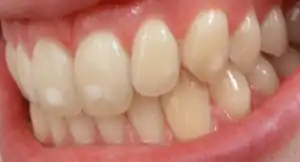

Dental fluorosis may or may not be of cosmetic concern. In some cases, there may be varying degrees of negative psychosocial effects. The treatment options are:

- Mild cases: Tooth bleaching[14]

- Moderate cases: Enamel microabrasion (outer affected layer of enamel is abraded in an acidic environment)[14]

- Severe cases: Composite fillings, Micro-abrasion, Veneers, Crowns[14]